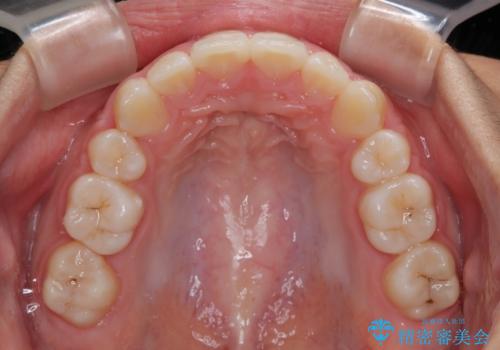

気がつくと唇があいてしまう ワイヤー装置での抜歯矯正

- 口元の突出感で口が閉じにくいとのことで来院された患者様です。

上下左右の第一小臼歯4本を抜歯し、ワイヤー装置での抜歯矯正を行うこととしました。

口元の突出感が解消され、睡眠時の口呼吸が改善されました。